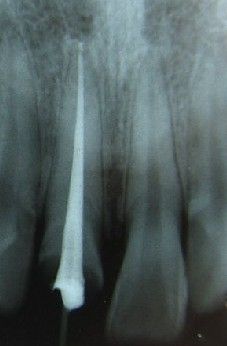

七、根管充填

封闭整个根管系统、堵塞主根管和侧副根管出口、防止微生物和液体的渗漏。无论是侧方加压法还是垂直加压法,应做到根管充填致密,根管充填后X线片上无根管腔隙,也不能超出根尖孔。立即咨询根管治疗价格<<

根管填充